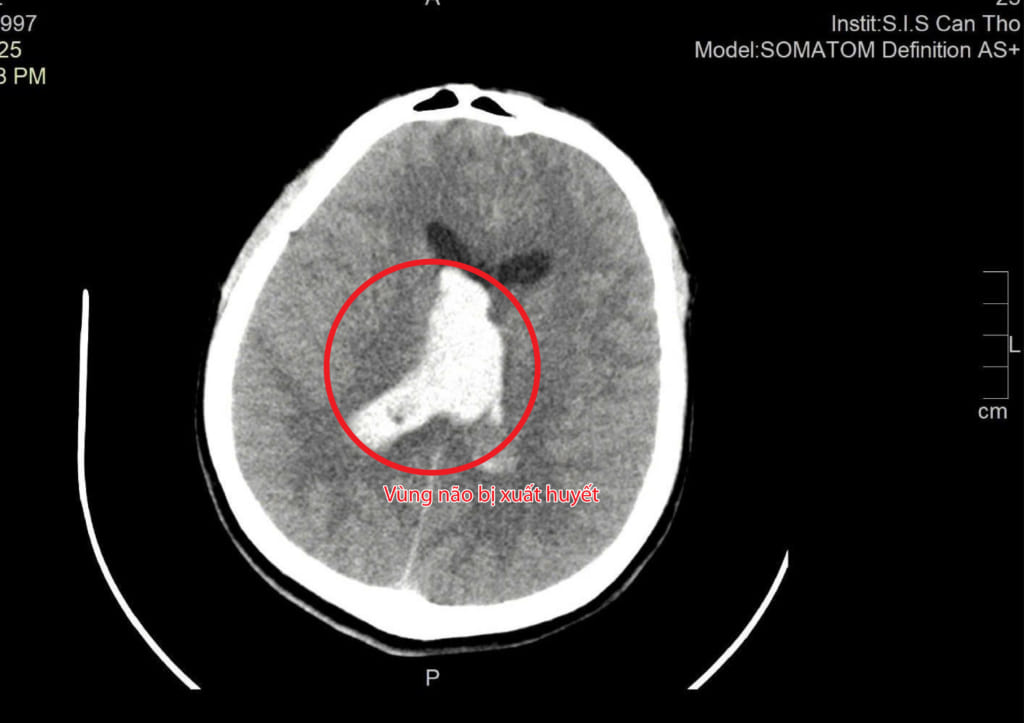

BS. Tôn Nữ Thị Điểm, khoa Ngoại tổng hợp chia sẻ: Sau khi tiếp nhận và cho chụp CT não, chúng tôi phát hiện bệnh nhân bị xuất huyết trong não và não thất, kèm phù não nặng. Nếu không được phẫu thuật kịp thời, áp lực nội sọ sẽ tăng nhanh, có thể đe dọa tính mạng.